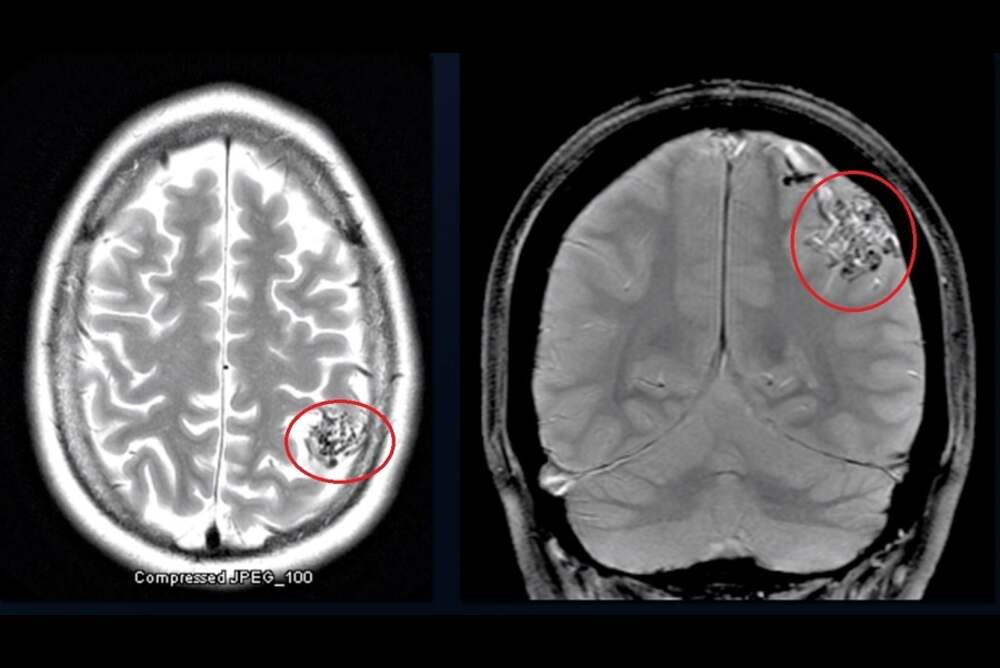

There is no evidence of cause of this condition that is not a result of environmental or lifestyle factors. Thus, the diagnosis is crucial and heavily depends on the area that is AVM Radiology. Modern imaging techniques such as MRI as well as CT angiography are employed to precisely determine the size of the malformation and location as well as pattern of flow. The precise radiological assessment is vital for precise guidance in subsequent treatment plans and to ensure a safe treatment strategy.

What is a Brain AVM?

A brain Arteriovenous Malformation (AVM) is an uncommon abnormal cerebral blood vessels. It interferes with normal blood flow through direct connections between veins and arteries that bypass the vital capillary system. This condition causes high-pressure blood flow in weak vessels, which are more prone to rupture. If untreated, the AVMs in the brain pose serious risk to health as the weak vessels can rupture in a way that could cause bleeding within the brain (hemorrhage) or stroke or irreparable neurological damage. Early diagnosis and treatment in a specialist AVM hospital such as IRFacilities are vital to prevent these serious problems and maintaining the neurological function.